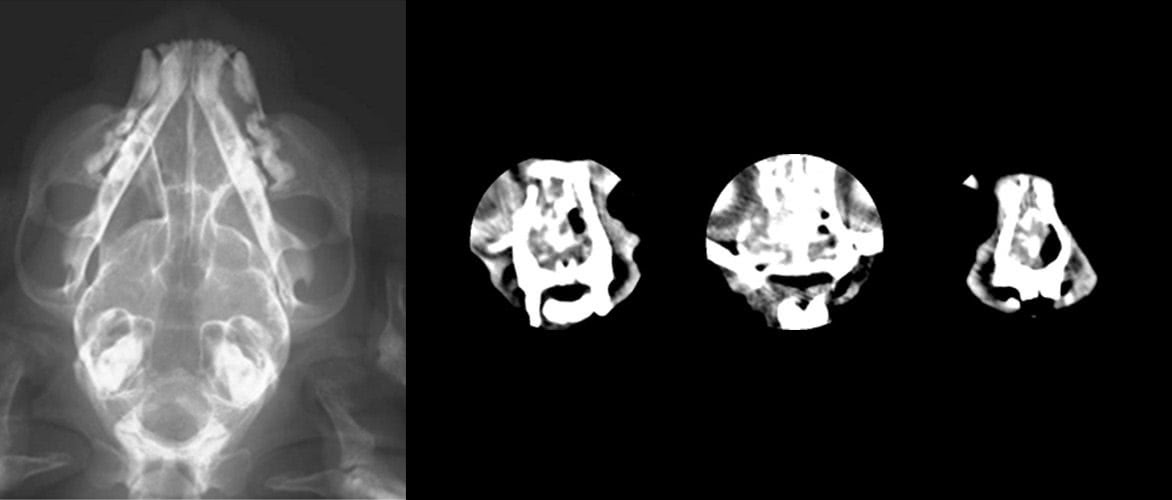

レントゲンにて腫瘍の存在は疑われたのですが骨浸潤は認められませんでした。ところがCT撮影を行ったところ鼻中隔・眼窩部の骨浸潤が確認できました。

歯肉の腫瘍は外見ですぐに確認できるものですがレントゲンで確認できなかった骨浸潤像がCTで確認できました。さらにこの腫瘍は眼窩底から眼球を上方に圧排していることが認められました。